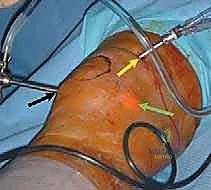

يُصنف هذا الإجراء تحت فئة "تحفيز نخاع العظم". عندما يكون هناك عيب غضروفي كامل السمك (أي أن العظم مكشوف تماماً)، يقوم الجراح باستخدام أداة دقيقة تشبه المخرز (Awl) لعمل ثقوب صغيرة في هذا العظم المكشوف.

هذه الثقوب تخترق الطبقة العظمية الصلبة (Subchondral bone plate) وتصل إلى نخاع العظم الغني بالأوعية الدموية. نتيجة لذلك، تخرج من هذه الثقوب قطرات من الدم والدهون تحتوي على مكونات سحرية: الخلايا الجذعية الميزنكيومية (Mesenchymal Stem Cells - MSCs) وعوامل النمو القوية.

3. تبني أحدث التقنيات (مناظير 4K): لا يعتمد الدكتور هطيف على الطرق التقليدية فحسب، بل يستخدم أحدث أجهزة المناظير بتقنية 4K، والتي توفر رؤية مكبرة وفائقة الوضوح لأدق تفاصيل الغضروف، مما يسمح بإجراء تنظيف دقيق وعمل ثقوب مثالية دون الإضرار بالأنسجة السليمة المحيطة.